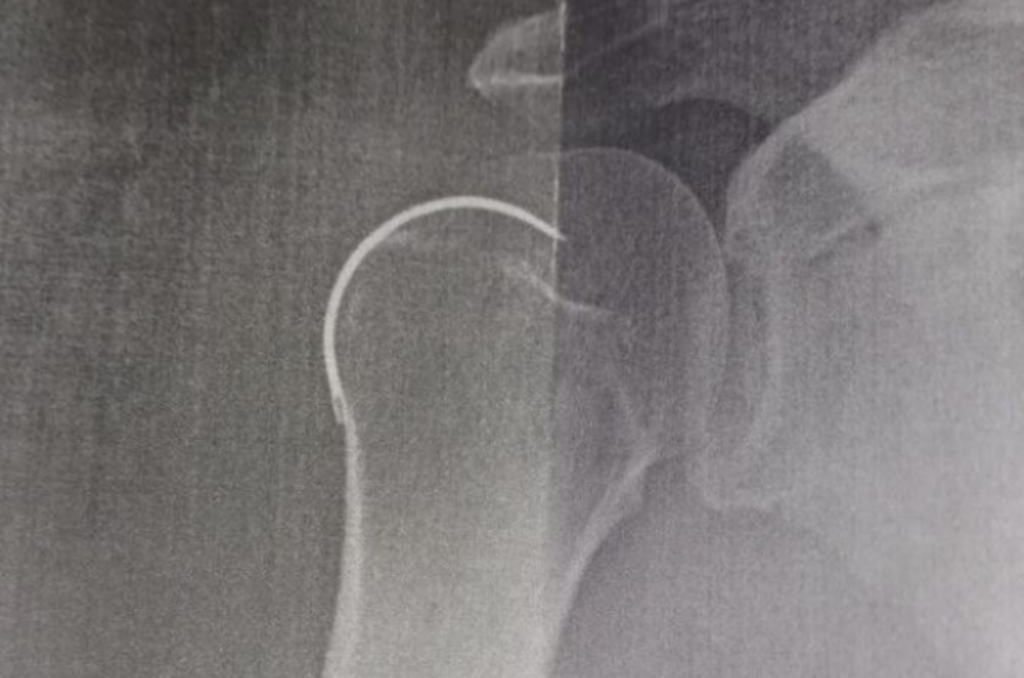

Um morador de Capivari de Baixo, de 62 anos, teve uma agulha esquecida dentro do corpo após uma cirurgia no seu ombro direito no Hospital Santo Antônio, em Armazém.

Ele passou por um procedimento no dia 6 de outubro do ano passado e somente na última semana é que o item foi retirado. Segundo ele, o médico teria esquecido a agulha de sutura dentro do ombro.

De acordo com o portal Sul Agora, ele enfrentou dores constantes por cinco meses, mas os médicos informavam que era comum do pós-operatório. No entanto, ao realizar um novo raio-X, os médicos descobriram a presença do objeto cirúrgico esquecido no paciente.